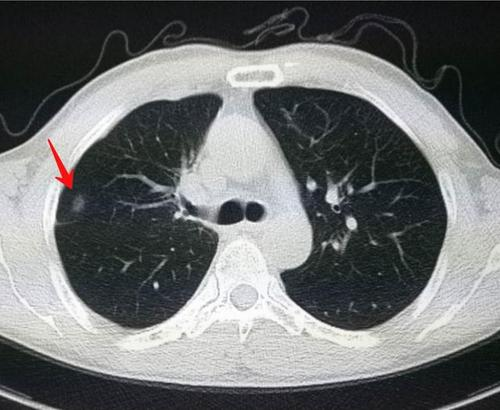

随着CT分辨率的逐渐提高,肺结节的检出率越来越高。

肺结节是在影像学检查中发现的肺组织中的异常密度影。

它们的形态可以是规则的,比如圆形或椭圆形,也可以是不规则的。

其中大多数肺结节是良性的,比如炎症、纤维化的疤痕或陈旧性结核留下来的钙化灶。有一些是肺癌的癌前病变,比如不典型增生。也有少数肺结节是恶性的,即我们所说的肺癌。